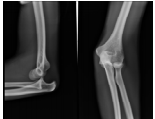

50 某 20 歲男性騎車跌倒,送醫後肘部 X 光如圖所示,下列敘述有幾項正確?①後脫位較常見 ②肘部 的三點骨突標誌分別是肱骨內、外上髁及尺骨鷹嘴突 ③如圖所示 X 光片為前脫位 ④肘關節又名 曲月秋 骱 ⑤《傷科補要》提及拔伸屈肘法復位:

「其骱若出,一手捏住骱頭,一手拿其脈窩,先令 直拔下,骱內有聲響,將手曲轉,搭著肩頭,肘骨合縫,其骱上矣」 (A)5 (B)4 (C)3 (D)2